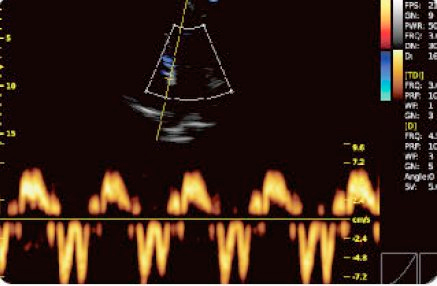

Doppler tissulaire (TDI)

- TDI est une technologie d'échocardiologie qui mesure le niveau direct de la vitesse myocardique ventriculaire gauche et droite.

- Accélère les processus au début du traitement du patient.

- Le TD diastolique reflète l'état du myocarde au repos.